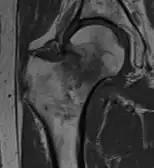

4) Данные рентгенологического обследования — выполняется рентгенография тазобедренного сустава в прямой проекции. Наличие линии перелома на рентгенограмме служит окончательным, объективным подтверждением предварительно выставленного диагноза. Иногда для постановки диагноза может потребоваться магнитно-резонансная томография или компьютерная томография.

В большинстве случаев достаточно выполнения рентгенограммы в прямой проекции. В ситуациях, когда есть подозрение на перелом шейки бедра, но оно не выявлено на рентгеновском снимке, следующим методом исследования является КТ. В редких случаях для подтверждения диагноза используется МРТ - диагностика.

Случай, демонстрирующий возможный порядок исследования изначально незаметных проявлений: